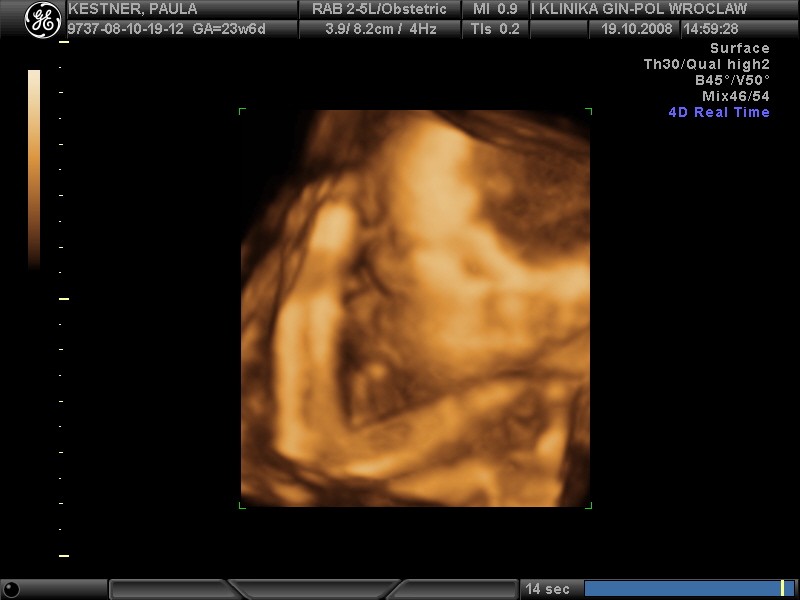

hej dziewczynki świerzo po wizycie wklejam fotki mojej córci(chyba dziewczynka....nie potwierdzone...ułożenie pośladkowe) to juz 24 tc+1 dzień